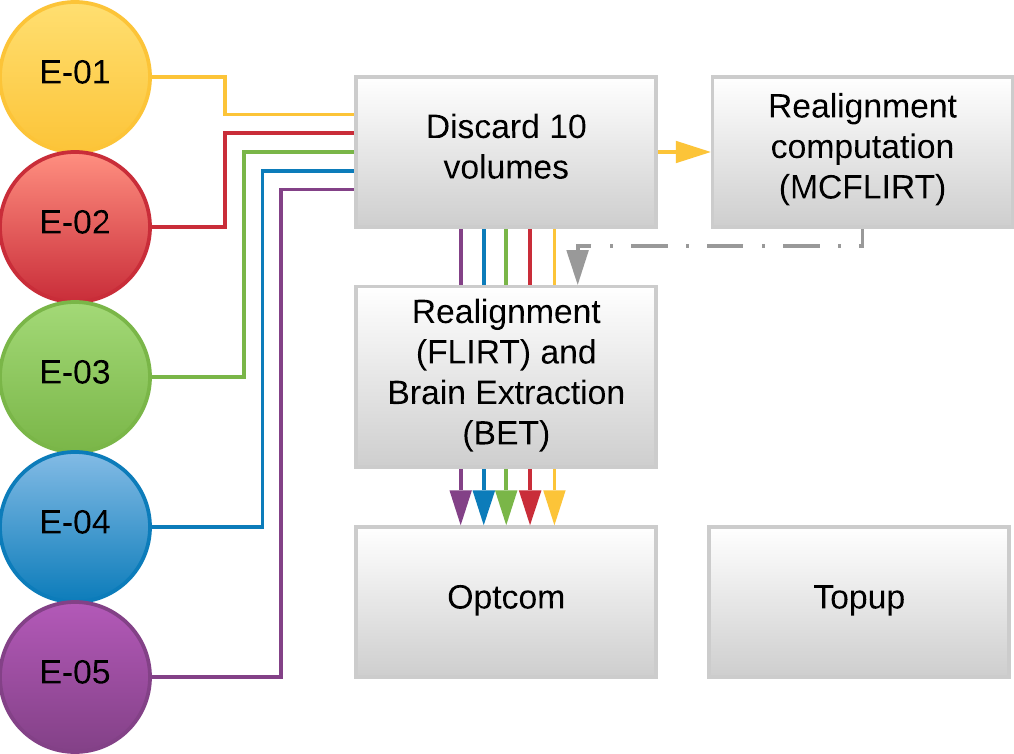

Methods: Preprocessing

- MP2RAGE and T2w skullstripped (AFNI)

- MP2RAGE normalised to MNI152 template (ANTs)

- T2w registered to MP2RAGE and to SBREF (FSL)

- MP2RAGE segmented and GM registered to SBREF (ANTs)

- GM eroded (FSL)

- EPI realigned to SBREF, saved the motion parameters (ANTs)

- EPI skullstripped (FSL)

- EPI distortion corrections (FSL)

Methods: preprocessing

Functional:

- motion realignment

- skullstripping

- optimal combination (OC)

- distortion correction